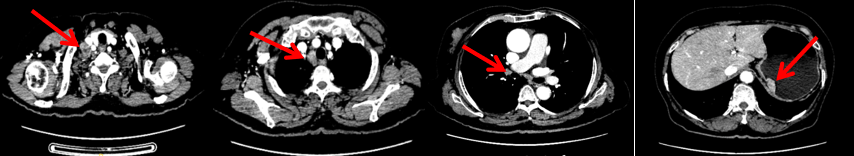

颈胸腹盆腔CT

右乳外上象限占位,考虑乳腺癌;右侧锁骨上、上纵隔及右肺门多发淋巴结转移(较大者24*15mm)。胃贲门处小弯侧胃壁明显增厚(26*12mm),考虑胃癌可能,周围脂肪间隙清;颈部未见明确异常。头颅MR未见脑转移。